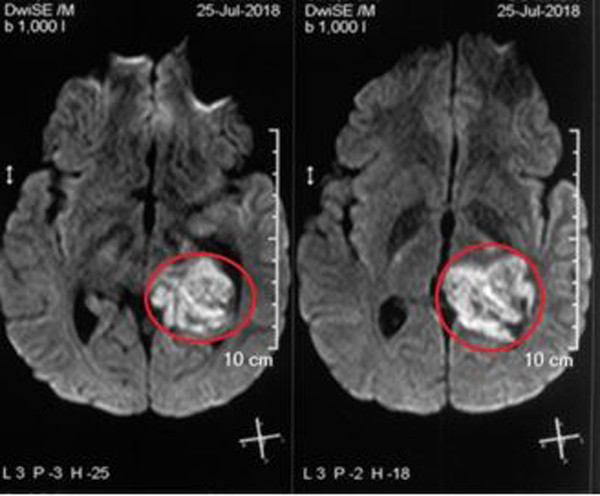

| U tá tràng kích thước khoảng 3cm trong lòng tá tràng |

Khi thăm hậu môn trực tràng, bác sĩ không phát hiện bất thường, không có máu. Tiếp tục chỉ định nội soi đường thực quản – dạ dày – tá tràng, các bác sĩ rất bất ngờ khi đoạn D2 tá tràng có khối lồi kích thước khoảng 3cm, nghi ngờ ung thư tá tràng.